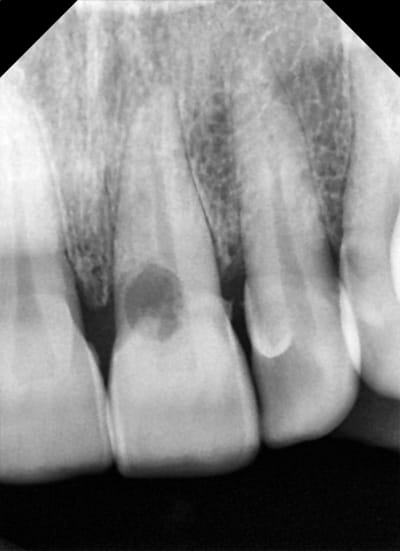

une autre radio qui explique un peu le dépassement, (enfin ça m'arrange de le penser) condensation trop forte pour avoir aussi les canaux accessoire.

015 hboxvo - Eugenol